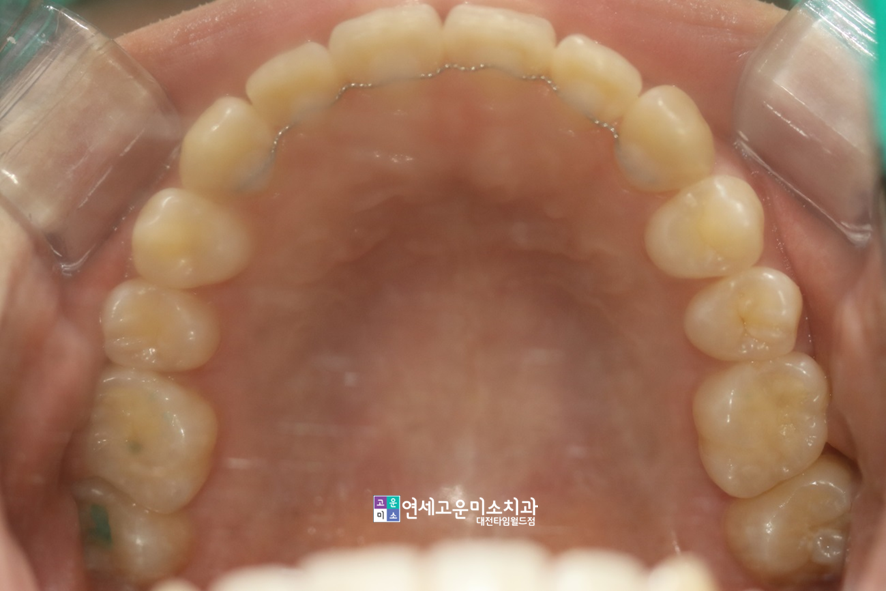

상악 좌측 두번째 앞니를 배열하고자

어금니를 뒤로 충분히 밀어주었으며,

그 옆에 앞니는 오른쪽으로 움직여서

적정 수준의 공간을 확보하였습니다.

이동 방향을 설정하는 데에 있어

중심선과 향후 교합을 고려했습니다.

하악에서는 오른쪽 앞니 두 개를

가지런한 상태로 배열하기 위해서

어금니를 후방으로 이동시켜주면서

그 옆 앞니를 왼쪽으로 보냈습니다.

이건 약간 전문적인 부분이지만

상악 앞니 4개가 많이 내려와서

웃을 때 잇몸이 노출되는 모습도

치료 전에 함께 확인되었습니다.

교정 후 치아 4곳의 높이를

적절한 수준으로 맞춰주었습니다.

그러면서 웃을 때 치아나 잇몸이

드러나는 정도가 개선되었습니다.